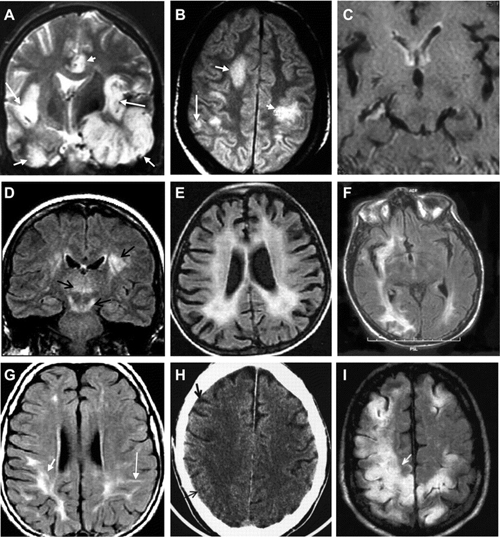

Din pacate, spun unii, cercetarea citata de toata lumea ca referinta pentru descrierea cazului lui Houben, nu contine niciun fel de date in masura sa permita cunoasterea reala a starii de sanatate a belgianului, ca de altfel nici a celorlati pacienti implicati in studiu. Doar concluziile sunt clare: utilizand un protocol de evaluare mai atent decat cel actual (bazat pe Scala Glasgow), combinat cu tehnici de neuroimaging, echipa lui Laureys ar fi descoperit ca 27% dintre pacientii aflati in coma acuta si 44% dintre cei in coma cronica ar fi si „victimele” unor diagnostice eronate.

Asadar, in cazul belgianului, in prima faza, prin intermediul noii tehnologii de „scanare” cerebrala, specialistii au putut demonstra ca activitatea cerebrala a acestuia nu era intrerupta. Intr-o a doua etapa, utilizand un instrument extrem de sensibil, in masura sa inregistreze si cele mai minime miscari, ei au putut „sa vorbeasca cu Rom”.